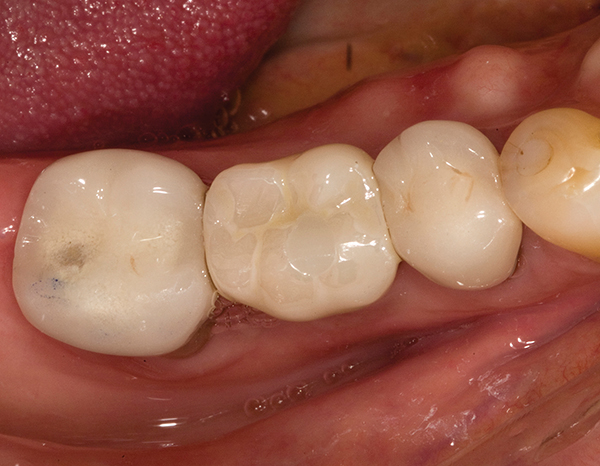

A mandibular right first molar was extracted due to an advanced Class III furcation and an irreversible pulpitis—a combination lesion. An immediate implant placement protocol was elected, and a PEEK abutment was placed on the implant (Figure 1). After 3 months of healing, a scan body was placed on the osseointegrated implant (Figure 2 and Figure 3), and an intraoral scan was taken (TRIOS Pod) (Figure 4) for the fabrication of a screw-retained crown.

Fig 1. Immediate implant placement with a PEEK healing abutment to contour soft tissue, mandibular right first molar.

Figure 1